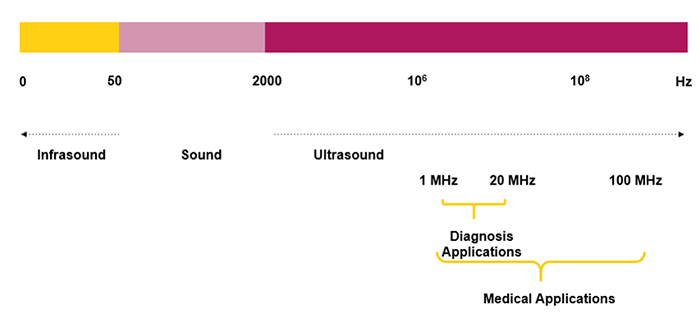

The human ear is not sensitive to ultrasonic vibrations:

- Audible Sound: 20 Hz < F < 20 kHz

- Ultrasound: 20 kHz < F < 200 MHz

- Ultrasound for Diagnosis: 2-20 MHz

Frequency Scale

Here you can find the frequency scale of infrasound, audible sound, ultrasound, and the range of frequency used for the medical applications. As you can see, ultrasound waves are sound waves with frequencies higher than the upper audible limit of human hearing. The frequencies used for medical imaging are generally in the range of 1 to 20 MegaHertz.